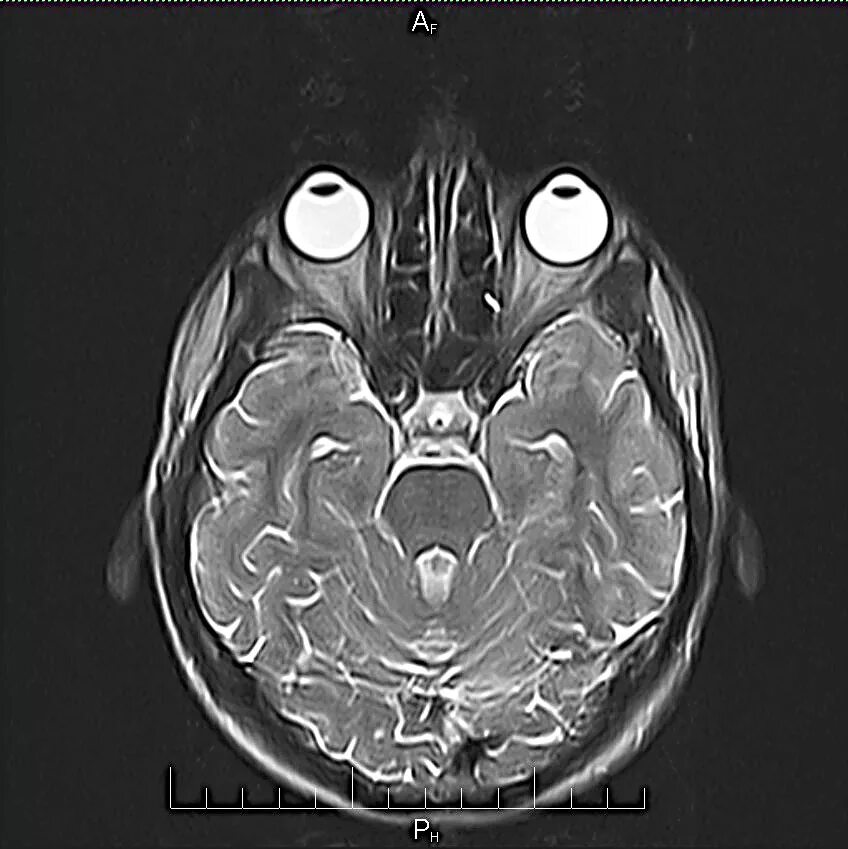

Томограмма глаза